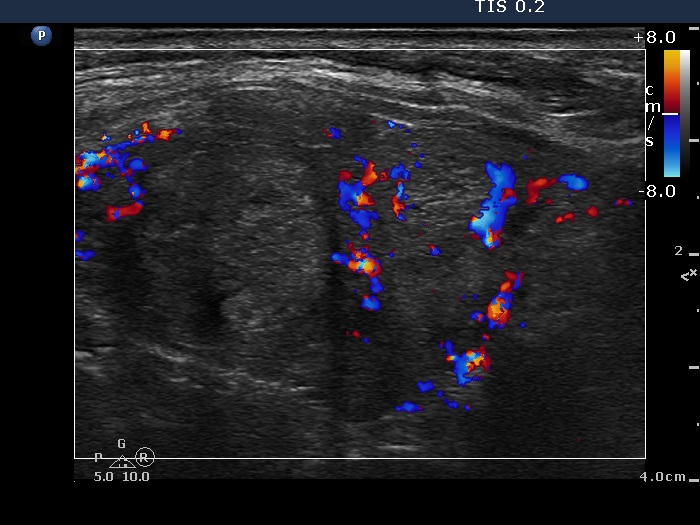

Follow-up investigation 6 months after first visit (ultrasonographic picture 7)

Right lobe, longitudinal scan, color Doppler mode. The vascularization is moderately increased.